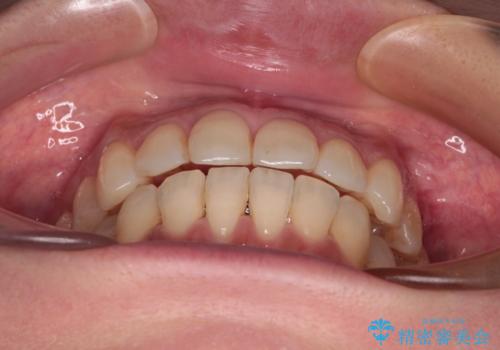

インビザラインによる矯正治療と奥歯のインプラント治療

- 全体的なデコボコと、以前抜歯した歯のスペースを閉じた部分が気になるとのことで来院された患者様です。

左上第一大臼歯を抜歯した際に、スペースを閉じたそうですが、歯が傾斜してものが挟まって不快とのことでした。

インビザライン矯正で全体の歯列と整えるとともに、左上第一大臼歯部にはスペースを作り、インプラントによる補綴治療を行うこととしました。

歯の傾斜が改善され、インプラントによるクラウンが装着されたことで、物が挟まることもなくなりました。